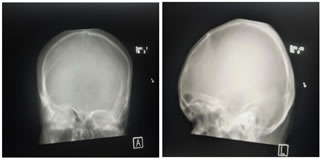

A 17-year-old female child was brought for deteriorated mental status and a history of few episodes of left focal seizures with secondary generalization since 2½ years. There was no history of head trauma. The seizure episodes were followed by decreased movement of the left side of the body and occasionally drooling of saliva from the left side. Perinatal vs. birth history was uneventful. The patient did not attend school. On examination, the child was undernourished with very poor cognitive function. Vitals were normal. Positive clinical findings noted were – microcephaly, severe mental retardation with an intelligence quotient of 40 and left-sided facial palsy. Examination of the central nervous system revealed left hemiparesis. Examination of other systems was unremarkable. Radiographs of skull showed thickening of the right hemicalvarium [Figure 1]. Non-contrast computed tomography and magnetic resonance imaging (MRI) reveled unilateral atrophy of the right cerebral hemisphere and ex- vacuo dilatation of ipsilateral lateral ventricle with prominence of sulci [Figures 2 and 3]. Thickening of the right hemicalvarium was noted measuring 7-8 mm compared to 5 mm on the left side (in frontal region at level of lateral ventricles) and enlarged right frontal sinus. These findings were suggestive of DDMS.

Figure 1: Skull radiographs: Anterioposterior and lateral views showing thickening of the right hemicalvarium (asterisk *); Figure 2: Axial sections of non-contrast magnetic resonance imaging (T1) and computed tomography (brain window) of the brain showing diffuse atrophy of the right cerebral hemisphere with ex-vacuo dilatation of the right lateral ventricle and prominence of sulci over the right cerebral hemisphere. Compensatory thickening of the right hemicalvarium is also seen; Figure 3: Coronal (T2) Magnetic resonance imaging and axial computed tomography(bone window) of the brain showing diffuse atrophy of the right cerebral hemisphere with ex-vacuo dilatation of the right lateral ventricle and compensatory thickening of the right hemicalvarium